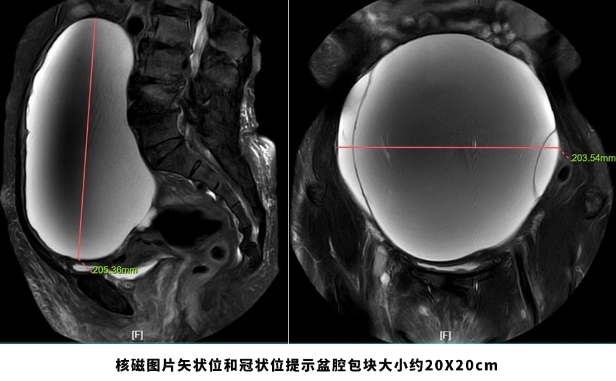

今日头条网页版:69岁老妇挺着“大肚子”来医院,检查后竟“怀”了个巨大肿瘤!